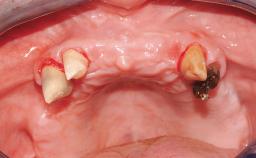

Rehabilitating an Edentulous Maxilla with a Fixed Dental Prosthesis Following Provisional Immediate Loading

This case features the flapless computer-guided placement of 7 bone-level implants, distributed to provide maximal support for the prosthetic framework. A rigid one-piece metallic framework was utilized as an interim restoration to reduce the risk of fracture associated with this prosthetic design. As part of the clinical examination, the SAC Assessment Tool was used, resulting in a surgical and restorative risk classification as “complex”.

Case Type Edentulous Maxilla

# of Implants 7

Guided Surgery Yes